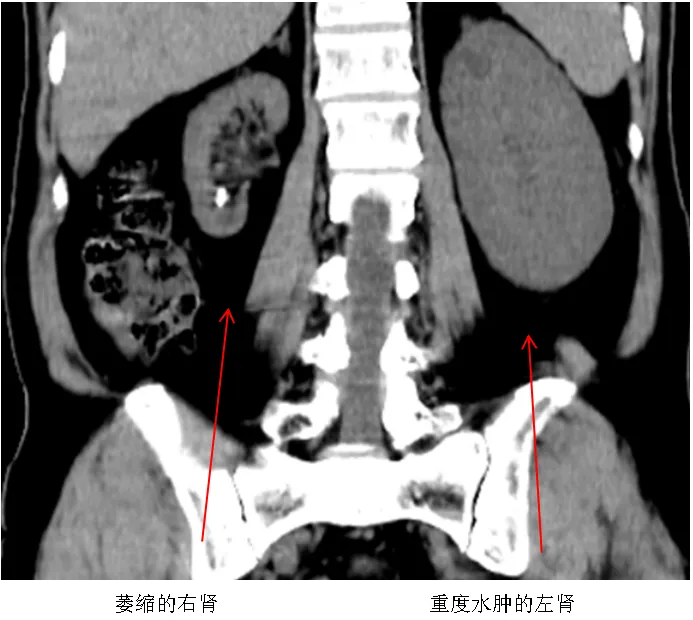

该院外科目前主攻方向为泌尿外科,近日,接诊一例特殊尿路结石患者,该患者男性,63岁,因“反复腰腹阵发性绞痛20余年,伴少尿2天”入院,诊断为左输尿管下段结石并重度积水,肾后性急性肾功能衰竭,右肾萎缩。血肌酐826.25μmol/L高出正常值约8倍,尿素24.12mmol/L高出正常值约3倍,最初患者及其家属对此危重病情缺乏认知,经医师反复解释病情,仍不接受手术治疗,该院立即启动应急预案,由分管副院长亲自与家属进行耐心细致地病情解释,最终获得患者及家属的理解,签订手术同意书。

手术采用输尿管镜下双J管植入术,术程顺利,术后2小时患者尿量、血肌酐、尿素等重要指标逐步恢复正常,病人转危为安。